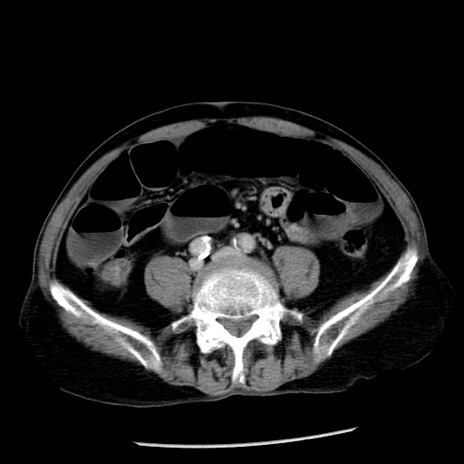

症例26(横断像)

冠状断像

【症例】80歳代男性

【主訴】嘔吐

【現病歴】昨晩2回嘔吐あり、今朝になっても嘔吐あり。来院。

【既往歴】胃潰瘍

【身体所見】意識清明、BT 37.6℃、BP 166/95mmHg、HR 100bpm、SpO2 97%、腹部:平坦・軟、腸蠕動音聴取良好、圧痛なし。

【データ】WBC 21900、CRP 1.46